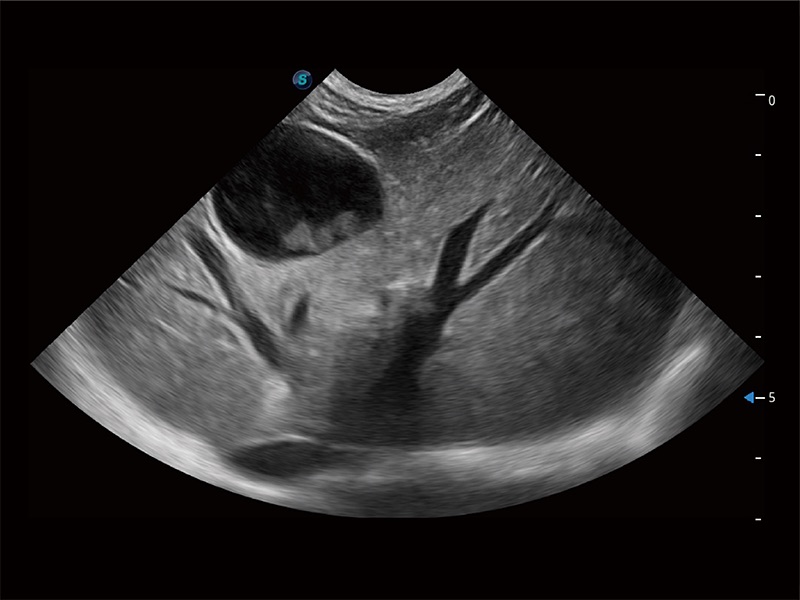

ProPet 80 配备了丰富的心脏探头群、先进的成像技术和专业的心脏测量工具,可帮助动物医生为不同体型和生理结构的动物提供心脏和心肌功能的全面评估。

提供解剖示意图、标准超声图像、扫查手法涂和操作者实时检查图像,指导操作者进行标准切面的正确扫查。